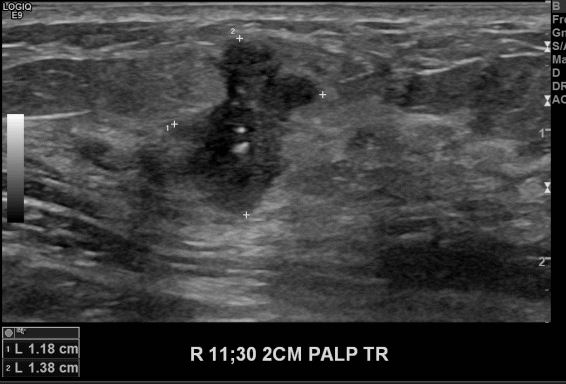

상기환자 건강건진상 우측 유방 이상소견으로 내원하신 40대 여성분으로 본원 초음파상

우측유방 11시 30분 방향에서 2cm 떨어진 거리의 만져지는 멍울 조직검사 시행하여

우측 침윤성 유관암 진단되었습니다.